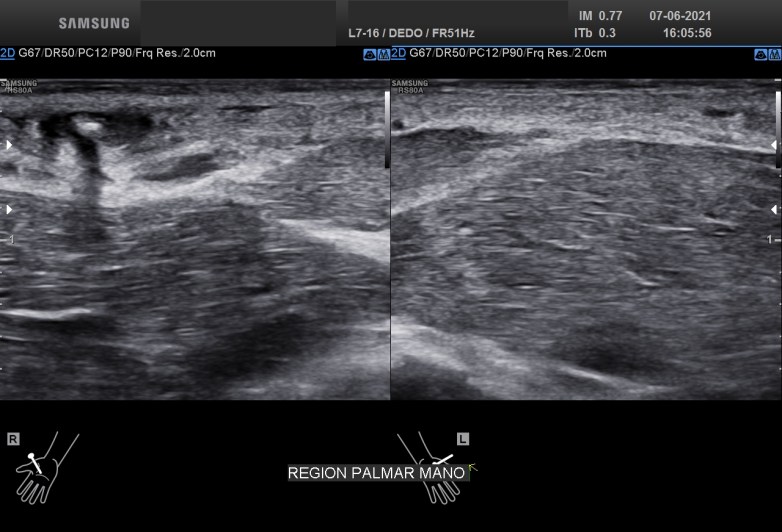

La imagen 5 y 6 te la pongo para que puedas ver como es el tejido afecto con el tejido conservado normal. Son Comparativos. Como la ecoestructura normal del TCS está respetado e integro. La musculatura y los vasos comparados y documentados con sus respectivos pictogramas.